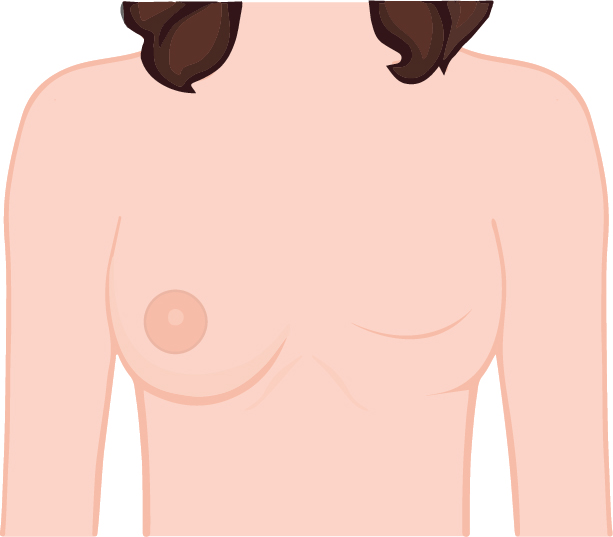

คนที่เป็นมะเร็งมี 2 แบบ บางคนตัดเฉพาะเนื้อ โดยที่หัวนมกับปานนมไม่ได้ตัด แบบนี้เสริมด้วยซิลิโคนขนาดที่เราต้องการก็โอเคแล้ว

คนที่เป็นมะเร็งมี 2 แบบ บางคนตัดเฉพาะเนื้อ โดยที่หัวนมกับปานนมไม่ได้ตัด แบบนี้เสริมด้วยซิลิโคนขนาดที่เราต้องการก็โอเคแล้ว

แต่บางคนทำเสร็จแล้วต้องรออีก 6 เดือน แล้วค่อยมาแต่งบริเวณปานนมและหัวนม โดยการตัดหนังขึ้นมา หรือเรียกได้ว่า เสริมสร้างหัวนมใหม่ ให้เท่ากับฝังที่ไม่ได้ตัด